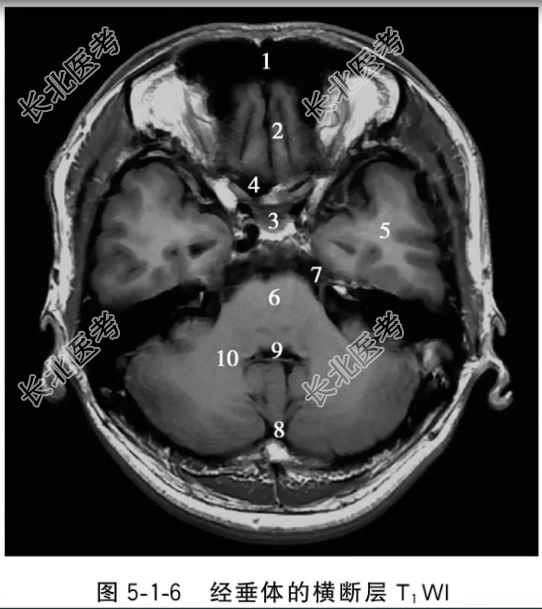

- 单项选择题经垂体的横断层T1WI中,标记为3的结构是

B、垂体